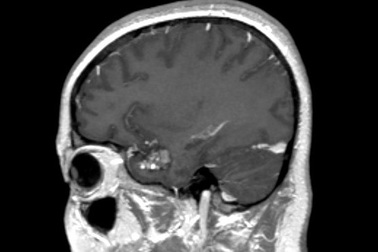

U máu thể hang tại nãoU máu thể hang là tổ chức bất thường của mạch máu não nhỏ (mao mạch), tạo thành bởi nhiều khoang, múi nhỏ giống như hình tổ ong hoặc hình quả dâu. Khoảng một nửa số các trường hợp có triệu chứng.

Đang khỏe mạnh, bé trai 11 tuổi bỗng lơ mơ, liệt tay chân sau dấu hiệu buồn nônKhoảng 20 ngày trước khi được phẫu thuật, bệnh nhi chóng mặt, buồn nôn... và cũng đã được gia đình đưa đến viện. Khi được đưa đến BV Việt Đức với mong muốn "còn nước còn tát", bác sĩ phát hiện khối u thân não chảy máu là nguyên nhân khiến bệnh nhân liệt tay chân, lơ mơ.